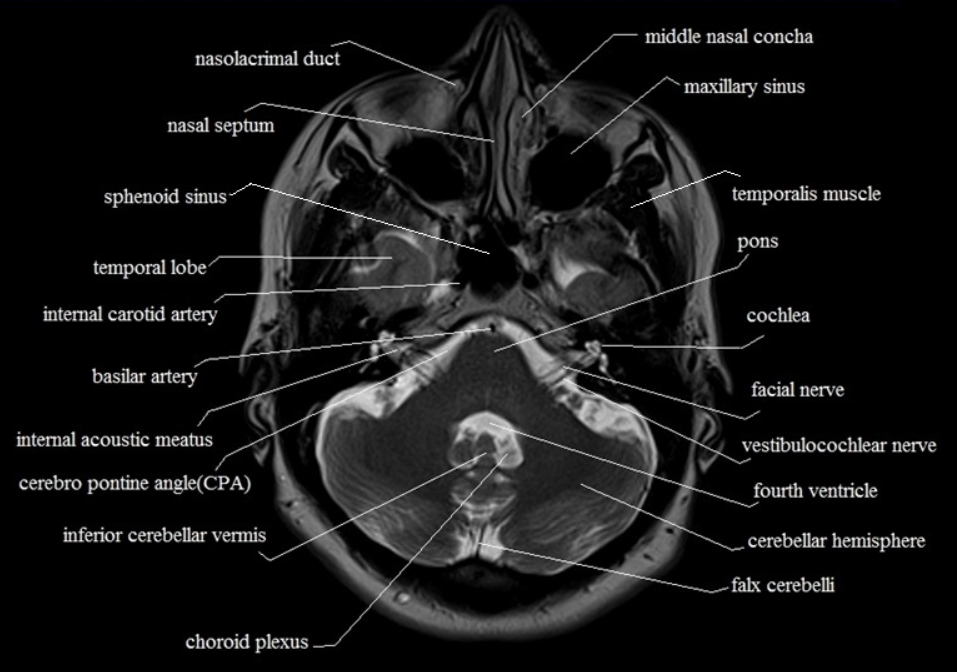

교뇌가 처음 나오는 컷이다. 교뇌는 소뇌과 연결되는 것처럼 보인다. 소뇌와 연결되는 부분처럼 나오는 level에서는 연수가 나온다.